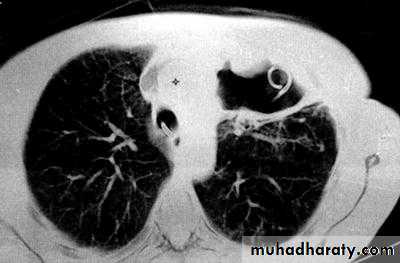

CXR : Air fluid level is only seen in upright filmCT san : clarify the diagnosis when the CXR is equivocal

• 6-CT scan